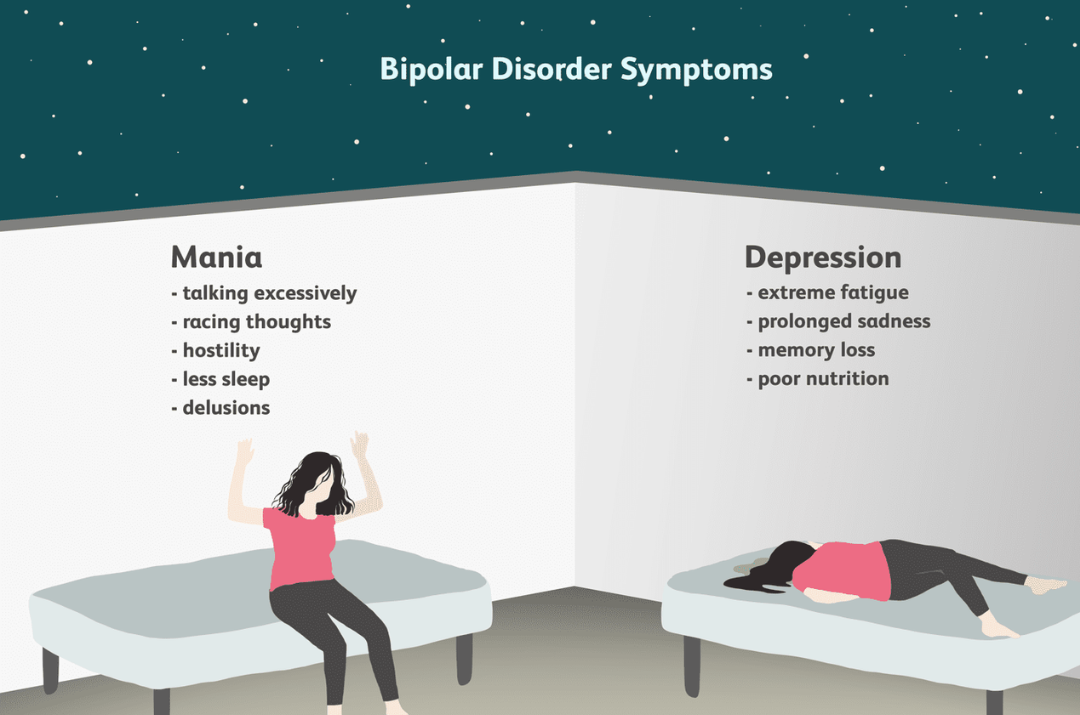

Disorders refer to abnormal conditions affecting physical or mental health, disrupting normal functioning. They can range from physical ailments like heart disease to psychological issues like anxiety. These conditions may be caused by genetics, environment, or lifestyle. Diagnosis often involves medical exams and tests. Treatment can include therapy, medication, or lifestyle changes to improve quality of life.

Disorders refer to abnormal conditions affecting physical or mental health, disrupting normal functioning. They can range from physical ailments like heart disease to psychological issues like anxiety. These conditions may be caused by genetics, environment, or lifestyle. Diagnosis often involves medical exams and tests. Treatment can include therapy, medication, or lifestyle changes to improve quality of life.